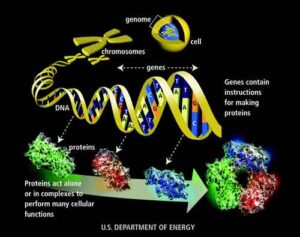

Quando gli animali vanno in letargo, anche il loro cervello va incontro ad una serie di modificazioni per affrontare il freddo e il lungo “sonno”. Al loro risveglio, con il ritorno alle temperature corporee fisiologiche, il ripristino delle normali attività cerebrali avviene anche grazie ad una proteina, RMB3, che è fondamentale per prevenire la perdita di connessioni neurali alle basse temperature e per favorirne lo sviluppo di nuove in primavera.

Questa proteina si attiva proprio in situazioni di shock termico, come hanno scoperto un gruppo di ricercatori dell’università di Leicester e dell’Università di Cambridge che, concentrandosi sui meccanismi di funzionamento di RMB3 sui topi con Alzheimer, hanno trovato che il ruolo protettivo della proteina sulle sinapsi potrebbe essere difettoso in caso di malattie neurodegenerative.

Questi trattamenti comportano però dei rischi per l’organismo e l’obiettivo dei ricercatori è proprio quello di comprendere i meccanismi scatenati dalla proteina RMB3 al fine di riuscire a riprodurne gli effetti di rigenerazione neuronale, per un eventuale futura applicazione alle condizioni neurodegenerative con l’obiettivo di limitare la perdita neurale.